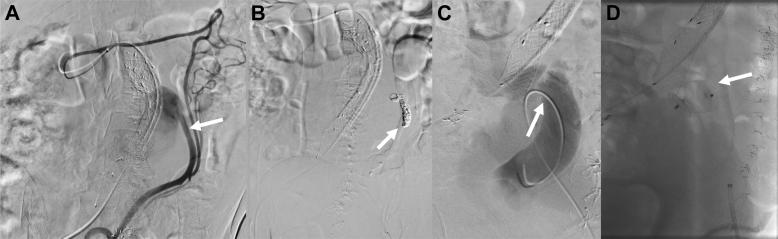

Staged endovascular repair of an abdominal aortic aneurysm adjacent to a chronic high-flow iliocaval traumatic arteriovenous fistula.

Large-vessel chronic traumatic arteriovenous fistulas are a rare complication after trauma. Delayed presentation can consist of one or more features of high-output cardiac failure, pulsatile abdominal mass, bruit, limb ischemia, and venous congestion. We describe a patient with a complex iliocaval fistula secondary to a remote gunshot wound associated with a large 8.5-cm aortic aneurysm. Informed consent of the patient was obtained for publication of the case.